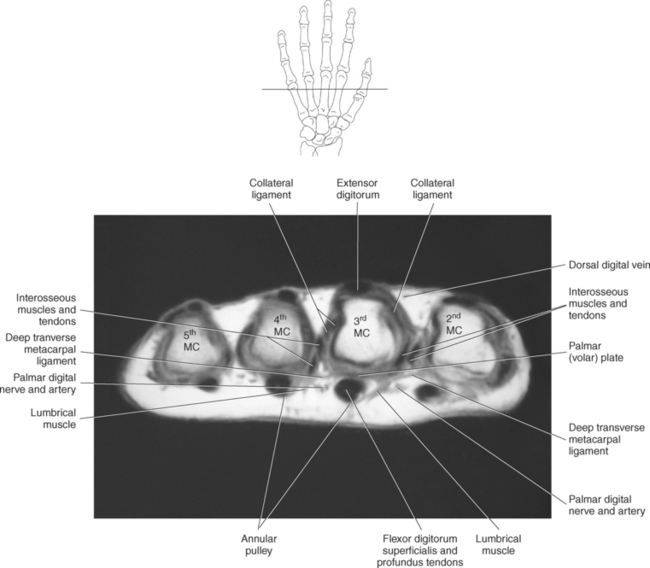

The bony anatomy of the wrist and hand consists of the distal radius and ulna, 8 carpal bones, 5 metacarpals, and 14 phalanges (Figure 9.101). Both the distal radius and ulna have a conical styloid process that acts as an attachment site for ligaments. The radial styloid process is located on the lateral surface of the radius, whereas the ulnar styloid process is located on the posteromedial side of the ulna. The carpal bones are arranged in proximal and distal rows. Located in the proximal row of carpal bones are the scaphoid (navicular), lunate (semilunar), triquetral (triquetrum), and pisiform bones. The pisiform is considered a sesamoid bone that is embedded in the tendon of the flexor carpi ulnaris. The distal row consists of the trapezium (greater multangular), trapezoid (lesser multangular), capitate (os magnum), and hamate (unciform) bones (Figures 9.102 through 9.114). The five metacarpals are small tubular bones with a proximal end (base), distal end (head), and shaft (body). The 14 phalanges that make up the fingers are short tubular bones. Like the metacarpals, each phalanx consists of a proximal (base), middle (body or diaphysis), and distal (head) portion. Each digit consists of 3 phalanges (proximal, middle, and distal), except for the thumb (first digit), which has only 2 phalanges (proximal and distal). The articulation of the phalanges of the second through fifth digits creates three interphalangeal joints: the metacarpophalangeal (MCP) joints classified as condyloid joints, proximal interphalangeal (PIP), and distal interphalangeal (DIP). The proximal and distal interphalangeal joints are classified as hinge joints (Figure 9.101). The first digit, which consists of 2 phalanges, has just two joints: the MCP joint, classified as a saddle joint, and an interphalangeal joint, classified as a hinge joint (Figure 9.101).

The joints of the wrist and hand are quite complex and consist of the following: distal radioulnar articulation, radiocarpal articulation (proximal joint of hand), midcarpal articulation (distal joint of hand), intercarpal articulations (articulations between proximal and distal carpals), carpometacarpal articulations (between carpals and metacarpals), the intermetacarpal articulations (between bases of metacarpals two through five) and the interphalangeal joints (between phalanges of each digit) (Figures 9.111 and 9.115). The distal radioulnar articulation, also called the distal radioulnar joint (DRUJ), is created when the ulnar notch of the radius moves around the articular circumference of the ulna, providing the movements of supination and pronation. The main stabilizing element of the DRUJ is an articular disk called the triangular fibrocartilage complex (TFCC). The TFCC is a fan-shaped band of fibrous tissue that originates on the medial surface of the distal radius and traverses horizontally to insert on the ulnar styloid process (Figures 9.115 and 9.116). It rotates against the distal surface of the ulnar head during pronation and supination and separates the ulna from the carpal bones. The proximal surface of the radiocarpal articulation is formed by the articular carpal surface of the radius and the TFCC, whereas the distal surface is formed by the articular surfaces of the scaphoid, lunate, and triquetrum and the interosseous ligaments connecting them (Figures 9.111 through 9.115). The midcarpal joint is formed by the articulations between the proximal and distal carpal rows (Figures 9.110 and 9.115). The articulation between the carpals within each row creates the intercarpal joints (Figures 9.111 and 9.115). The carpometacarpal joints are formed by the articulations between the carpus and the five metacarpals (Figure 9.111 and 9.115). The carpometacarpal joint of the thumb is an independent joint formed by the articular surfaces of the trapezium and first metacarpal, creating a pure saddle joint. The carpometacarpal articulations of the two to five digits are amphiarthrotic joints with little mobility (Figures 9.105 and 9.115). The intermetacarpal articulation exists between the base of the metacarpals and is joined by the palmar and dorsal metacarpal ligaments (Figure 9.115).

The MCP and interphalangeal joints each have a palmar ligament and two collateral ligaments. The palmar (volar) ligament is a thick, dense fibrocartilaginous tissue that covers the palmar surface of the joints. The palmar ligaments run between and are connected to the collateral ligaments, creating the floor of the interphalangeal and MCP joints. The deep transverse metacarpal ligament (DTML) consists of a series of short ligaments that connect the palmar ligaments of the metacarpal heads (Figure 9.123). The DTML prevents separation of the metacarpals. Along the palmar surface of the fingers, the ligamentous structures of the radial and ulnar collateral ligaments, radial and ulnar accessory collateral ligaments, and palmar plates provide stability for the MCP and interphalangeal joints (Figure 9.121). There is a fibroosseous tunnel along the palmar aspect of each finger for the passage of the flexor tendons. The tunnel is created by well-defined areas of thickening of the tendon sheath and is called the annular pulley system. It is composed of five annular pulleys and three cruciate pulleys, which are important structures that prevent the displacement of the tendons during flexion of the fingers (Figure 9.122). The dorsal surface of the hand and fingers contains the extensor mechanism or extensor hood (Figures 9.123 through 9.126). The extensor hood consists of the digital extensor tendon, extensor hood proper, and insertions of the lumbricals and interossei muscles and serves to maintain the integrity of the extensor tendons along the path of the MCP and interphalangeal joints.

The metacarpal muscle group includes the interossei and lumbrical muscles. There are seven short interossei muscles in the metacarpal muscle group: three single-headed muscles located on the palmar surface and four double-headed muscles located on the dorsal surface (Figure 9.141, A and B). The four palmar interossei muscles arise from the first, second, fourth, and fifth metacarpals and insert on the corresponding proximal phalanges, frequently radiating into the corresponding tendons of the dorsal aponeurosis. These muscles are responsible for flexion at the MCP joints and extension at the interphalangeal joints. The dorsal interossei arise by two heads from the sides of the five metacarpal bones to insert on the proximal phalanges and radiate onto the dorsal aponeurosis. Like their palmar counterparts, the dorsal interossei flex at the MCP joints and extend at the interphalangeal joints. The four small lumbrical muscles arise from the tendons of the flexor digitorum profundus and pass to the radial side of the corresponding finger to insert on the extensor expansion covering the dorsal surface of the finger (Figure 9.142). The lumbricals flex the first phalanges at the MCP joints and extend the second and third phalanges at the interphalangeal joints.